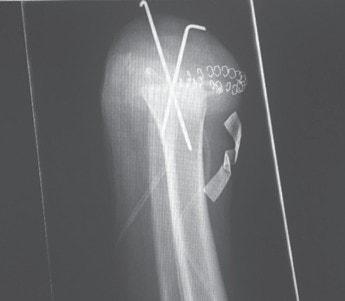

- Bei jeder Amputation handelt es sich um ein plastisches Verfahren mit großer Wund- und Narbenfläche und nicht um das bloße Abschneiden eines Extremitätenteiles. Die in der Spezialambulanz für Amputierte des Verfassers begutachteten Ergebnisse lassen aber vermuten, dass dies noch nicht allen Operateuren klar geworden ist (Abb. 3a–c).